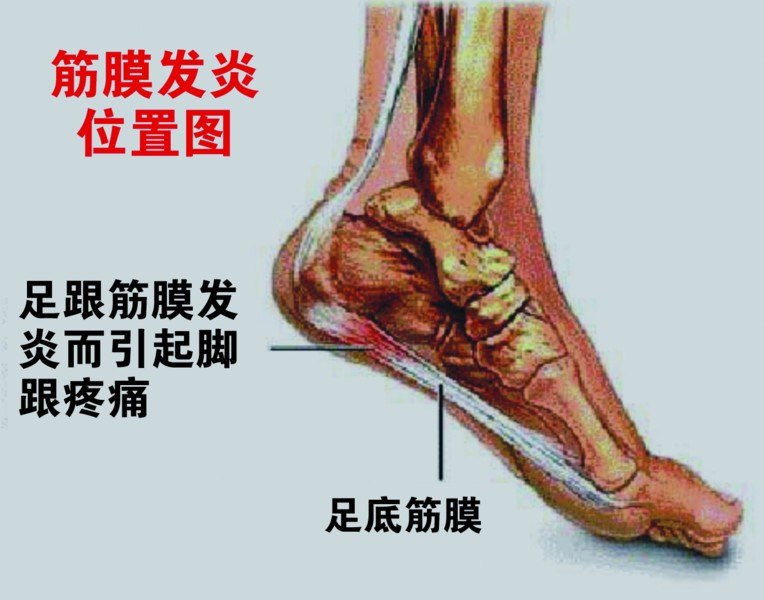

先来看看什么是跖底筋膜。

上图中白色的条索状的是肌腱和筋膜,其中位于脚底板的那一条就是跖底筋膜,红色的部位就是跖底筋膜的病变部位。所谓跖底筋膜炎,就是这条筋膜在脚后跟的止点处发炎了。实际上也并不全是因为炎症,更多时候是因为反复劳损、退变,引起的筋膜微小的撕裂口。

当我们走路抬起脚后跟时,前脚掌和地面接触并负重固定,后脚跟抬起,跖底筋膜被拉伸,天长日久,每天要走多少步,如此大量的反复的拉伸,逐渐导致了这条筋膜的病损。

跖底筋膜炎的疼痛位置一般在脚后跟的底部稍偏内,常常按压会有疼痛感,脚跟下面有固定的压痛点。